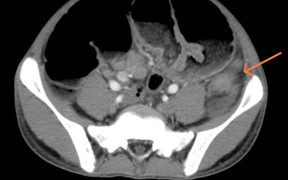

Kết quả xét nghiệm giải phẫu bệnh cho thấy người phụ nữ này bị ung thư tế bào đáy xâm nhập mô liên kết xơ. Người bệnh được các bác sĩ khoa Tai mũi họng phẫu thuật cắt bỏ u hắc tố chóp mũi để loại trừ tế bào ung thư phát triển ra vùng xung quanh.